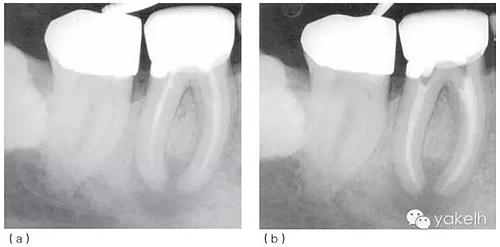

局麻下放置橡皮障隔離術(shù)區(qū),拆除現(xiàn)有修復(fù)體,去除樁周圍的核,使用超聲器械使樁松動并拔出。臨床檢查可見46遠中邊緣位于齦下2mm,DOM下觀察發(fā)現(xiàn)剩余牙體結(jié)構(gòu)完好且可修復(fù)。46臨時用不銹鋼帶環(huán)加固和玻璃離子水門汀充填(圖5.1.2a)。放置帶環(huán)的目的是容納充填材料并保護患牙的完整性。

2周后復(fù)診,患牙隔離和消毒同前;保持干燥(使用低速球鉆,避免污水再次進入患牙),去除暫封材料;次氯酸鈉和EDTA沖洗進行根管再預(yù)備;紙尖干燥根管;使用牙膠和根管封閉劑充填根管;在遠中根管內(nèi)預(yù)備樁道;窩洞用復(fù)合樹脂充填(圖5.1.2b)。

圖5.1.2(a)46根管再治療前X線片?,F(xiàn)有修復(fù)體、核及兩個不銹鋼樁均已安全拆除,患牙用不銹鋼帶環(huán)和Ketac-SilverTM臨時修復(fù),這為后續(xù)治療提供了無微滲漏且穩(wěn)定的局部環(huán)境。(b)46根管再治療后X線片。與圖5.1.1相比,根管預(yù)備和充填更接近理想的工作長度,致密度更高。